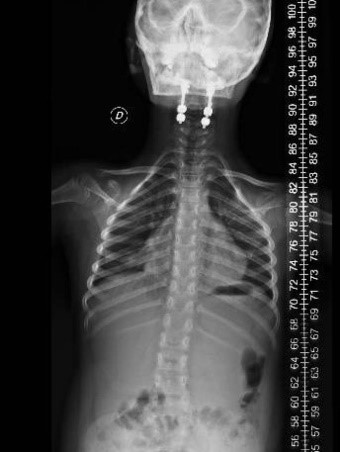

Se decide internación por síndrome medular agudo, y se realizan estudios por imágenes donde se observa lesión medular con mielomalacia debido a mal formación en charnela con inestabilidad atlanto axoidea y estrechamiento del foramen (Figuras 1, 2 y 3). En tomografía se observa agenesia del arco posterior del atlas con displasia de macizos laterales (Figura 4).

En el postoperatorio permaneció en terapia intensiva durante 48 horas y luego continuó su internación en sala de cuidados generales por 5 días. Sin complicaciones en el perioperatorio, con mejoría de su estado neurológico motor inmediatamente. Se retira halo chaleco a los 2 meses. Controles clínicos y radiográficos satisfactorios. En tomografía a los 6 meses se observan signos de fusión (Figuras 6 y 7).

Figura 6: Espinograma perfil postoperatorio

Figura 7: Espinograma posoperatorio